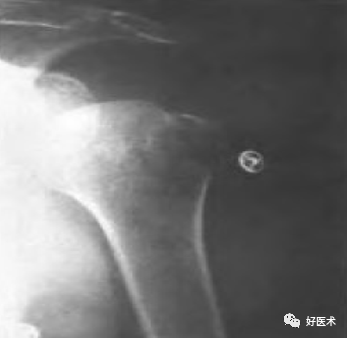

附:大结节撕脱骨折内固定

适用经手法复位失败,骨折移位超过1cm者;骨折块拉至肩峰下。

麻醉:颈丛麻醉 。

体位:仰卧位,患肩垫高与手术台成30°角。

操作方法:

切口:自肩峰外侧缘,约5cm,平行于三角纤维方向。

劈开三角肌纤维,切开三角肌肩峰和锁骨外侧端的附着点,显露结节部

在结节上用3.0钻头朝肱骨头方向钻孔,深约12-20mm

用钛丝穿过肩袖

将钛丝缠绕螺钉钉帽一圈

选择合适长度螺钉

拧入干预螺钉至钉帽外露3mm深度

用钢丝钳把钛丝缠绕拧紧,检查骨折复位情况

冲洗伤口,逐层缝合肌肉,皮肤切口

曲肘90°位三角巾悬吊制动,2周后开始被动活动